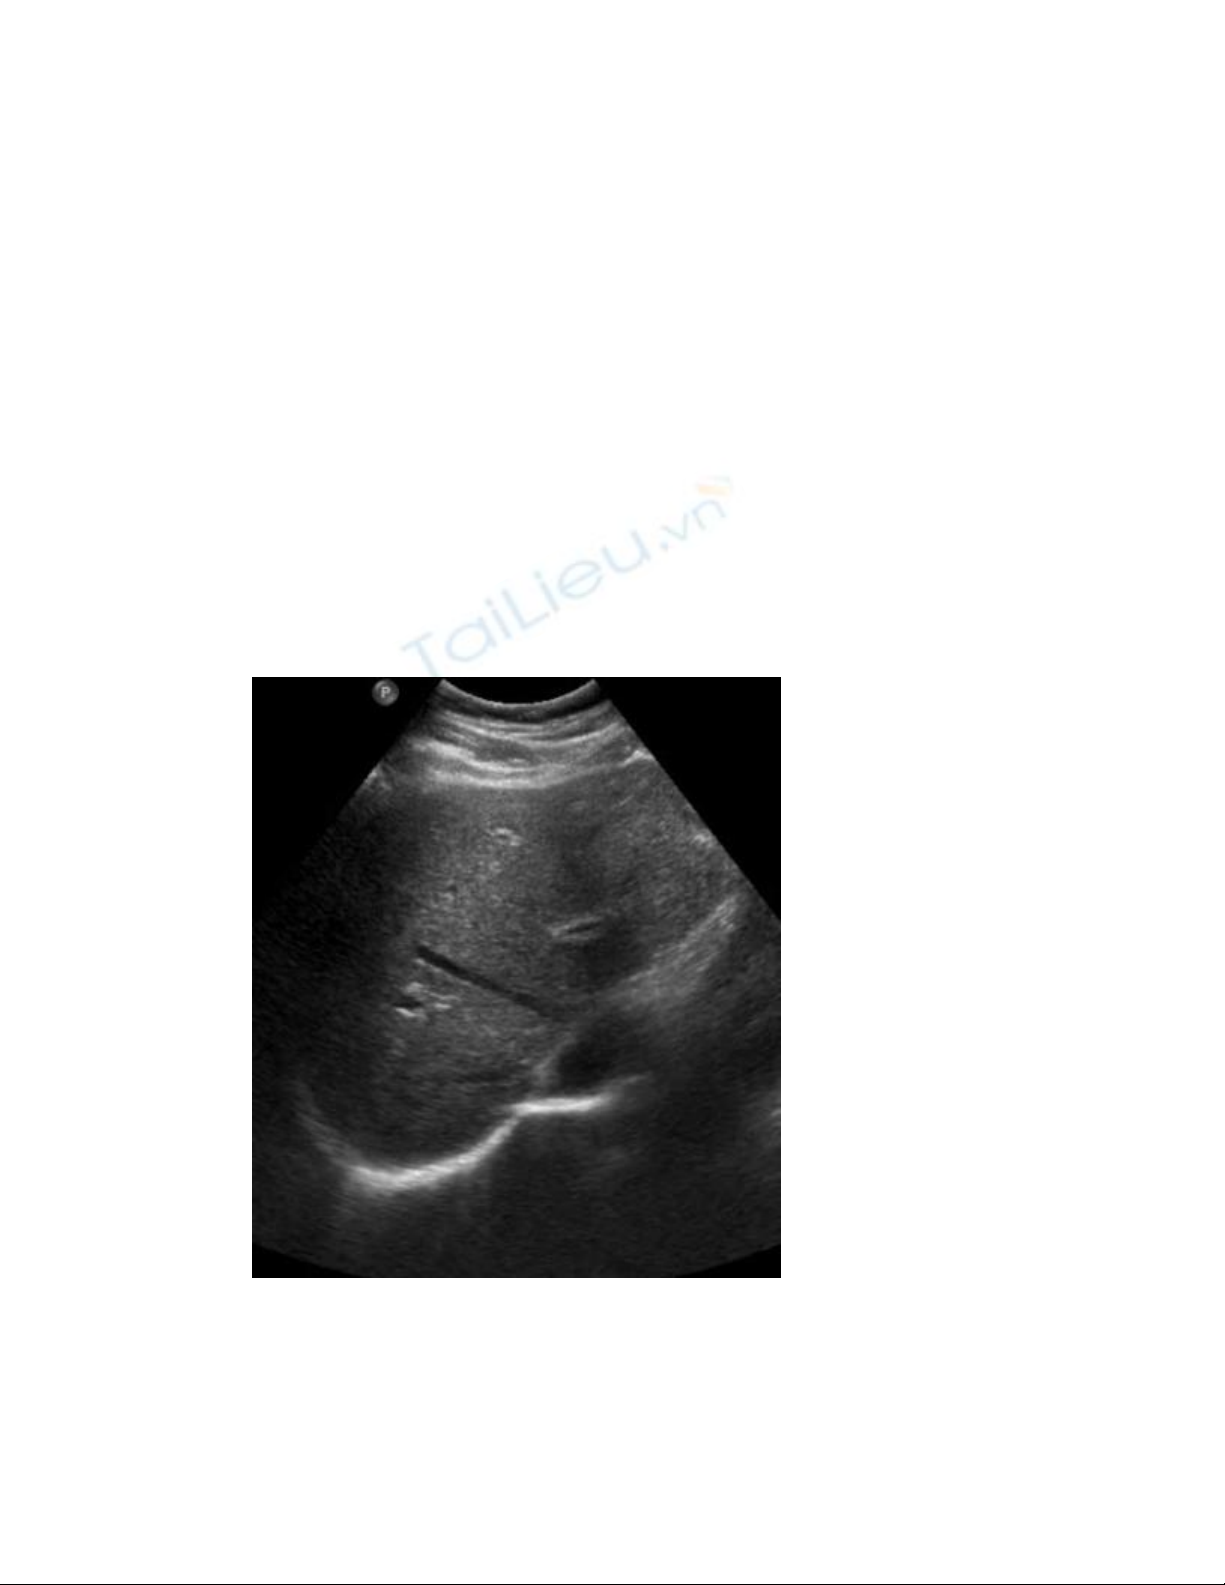

Hình ảnh siêu âm cắt ngang của gan:

Gan có kích thước, độ hồi âm và mẫu hồi âm bình thường.

Hình cắt ngang túi mật

Thành túi mật có độ dày bình thường, d#3mm